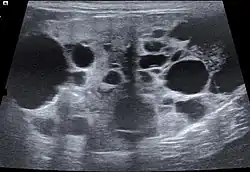

Cystic kidney in ultrasound image

PW-Doppler: Increased resistance index

The ultrasound examination allows morphological changes in the kidneys in more detail. In addition to changes in size and shape, renal cysts, localized (focal) organ damage, water sac kidneys and urinary retention as well as tumors can also be visualized. Hardly defined (diffuse) organ changes are accompanied by changes in echogenicity, but can only rarely be assigned to defined diseases.[22] Pulsed Wave Doppler" can also be used to detect circulatory disorders.[23] Calcification (nephrocalcinosis) is also common in chronic kidney disease and can also be detected sonographically.[24]